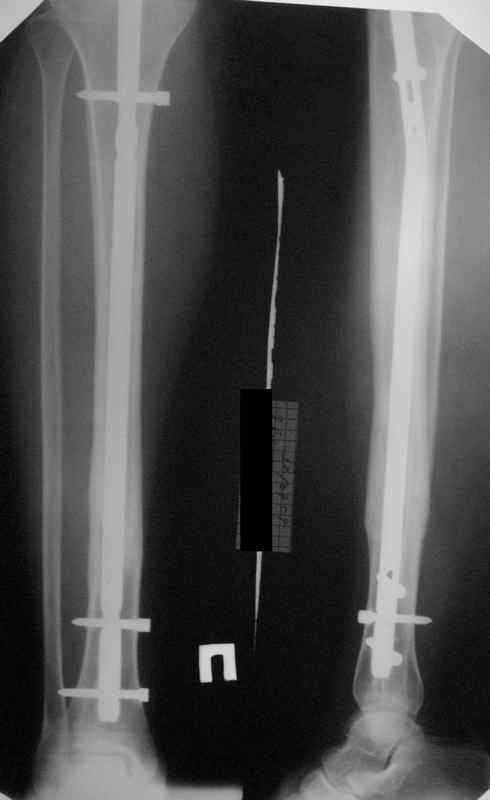

>СА> представленные снимки этому подтверждение-данный кососпиральный

СА> перелом репонируется идеально только открыто,что при БИОС не так существенно.

Здесь проблема не в идеальности репозиции, а в запасе усталостной прочности. Срастаться там может небыстро, диастазы довольно большие.

И когда еще и отломок короткий, и отверстие совсем рядом, это может привести к перелому стержня. За последние годы у нас было несколько пациентов, оперированных в других учреждениях с

подобным положением отломков, с такими переломами гвздей. И сейчас переделать куда как проще и легче, чем иметь дело со сломанным гвоздем.

Антон, дорогой, важнее вальгуса тут близость верхнего отверстия к перелому и отсутствие уверенности в быстром сращении из-за большого

диастаза.

В Кемпбелле можно прочитать, что Fractures in the distal third of the tibia had the highest frequency of nail breakage.

Вообще, этот вопрос обсуждался давно, и еще в статье R. Bucholz (1987) про переломы гвоздей указывалось, что расстояние от ближайшего отверстия до перелома должно быть не менее 5 см, иначе есть угроза усталостного перелома. По литературе переломы гвоздей в нижней трети

tibia достигают 4,3%.